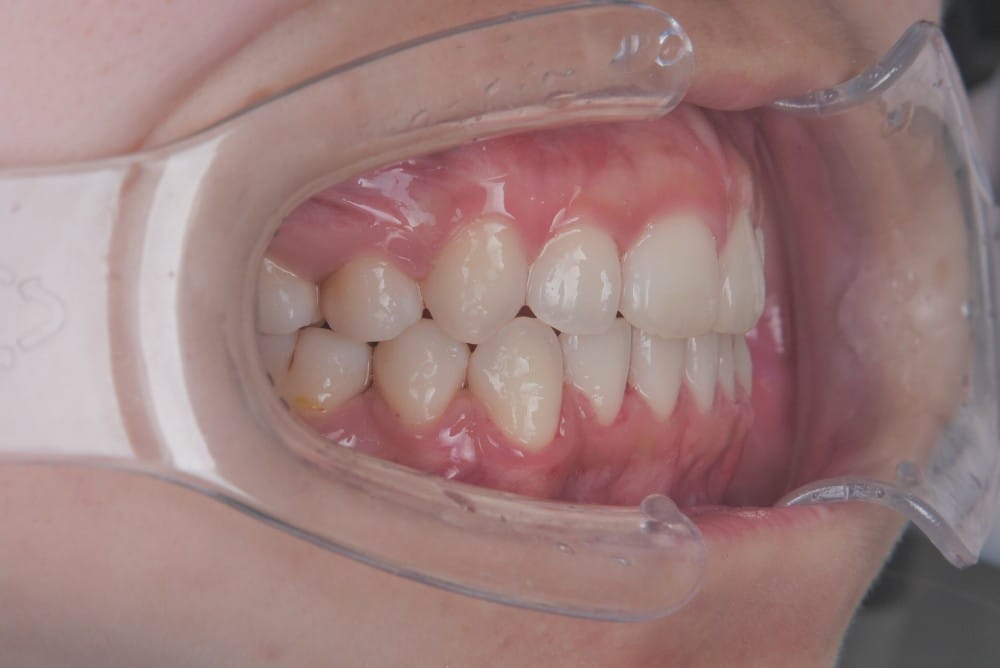

実際の治療前後の写真

before

after

前歯を数ミリ後退させるだけでも、唇の位置は明確に変わります。

横顔ではEラインとの距離が縮まり、「横顔がすっきりした」「口が自然に閉じられるようになった」と感じられる方が多いです。

また、歯の角度を適切にコントロールすることで、歯茎ごと前に出ているように見えていた印象が改善するケースもあります。歯列が原因であれば、外科手術を行わずに目標に近づける可能性が高いのです。

治療前後比較